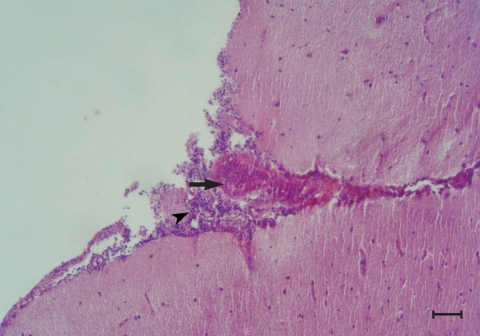

Histopathological changes were observed in organs of all the experimentally infected chickens at day 240 PI. Peribronchiolitis with infiltration of lymphocytes, and hyperplasia of bronchiolar associated lymphatic tissues (BALT) and goblet cells, were evident in the lungs of infected chickens (Fig. 1). Mild hemorrhages, lymphocytic infiltrations, and a few eosinophils were observed in the meninges, especially over the cerebellum (Fig. 2). Perivascular infiltration was seen around some of the vessels in the cerebral parenchyma in most of the infected chickens. Mild focal infiltration of lymphocytes was present between cardiac muscle fibers of the infected chickens. No lesions were seen in other tissues of the infected chickens. No abnormality was observed at gross and histological levels in the liver, lungs, kidneys, heart, brain, and other tissues examined of uninfected control chickens.